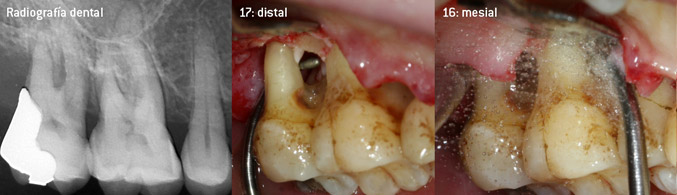

Como precursores del desarrollo de la nueva punta diamantada 3AP para eliminadores de sarro neumáticos, los dos odontólogos constataron que era necesario limitar el uso de las puntas diamantadas que se estaban comercializando hasta la fecha, sobre todo durante los tratamientos de furcaciones o en bolsas interradiculares estrechas. Además, esto debe llevarse a la práctica independientemente de si se trata de un procedimiento no quirúrgico (figura 2) o de un procedimiento quirúrgico (figura 3).

Fotos (figuras 2 -4): © Dr. Christian Graetz)